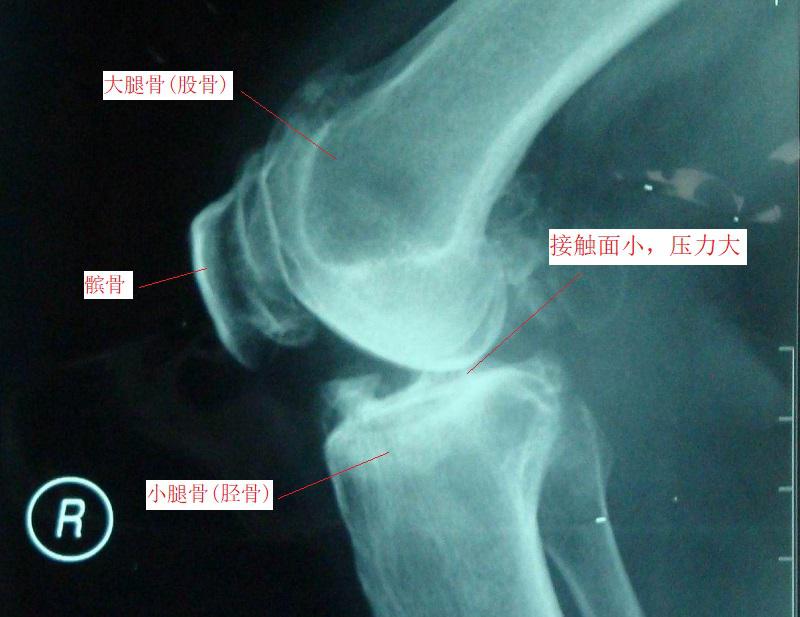

上下楼梯膝关节疼痛的原因 上下楼梯时,膝关节需要承受的压力更多,关节屈曲的角度较大(如下图1所示),大骨腿与小腿骨之间的接触面较小;髌骨承担“支点”的作用,并在负重的情况下滑动。骨与骨之间的作用力大幅增加。